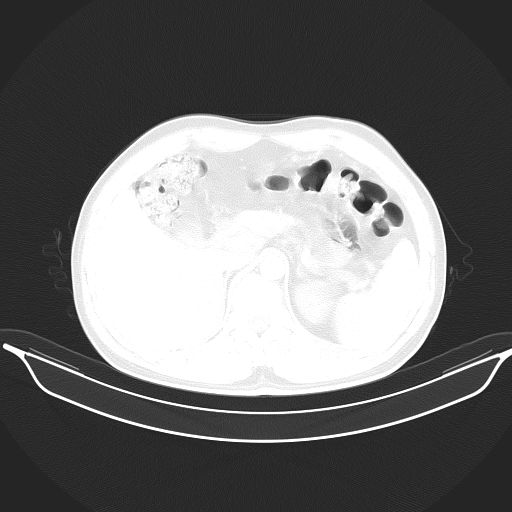

标题: CT25490:男,40岁,体检发现;无其它不适。 [打印本页]

标题: CT25490:男,40岁,体检发现;无其它不适。

考虑:1、过各敏性肺炎可能性大,建议定期复查。

2、轻度脂肪肝。